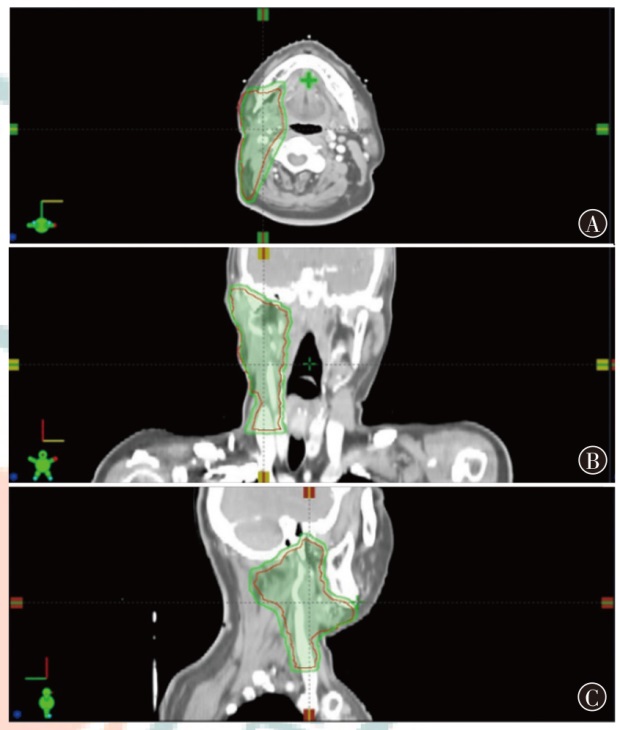

Objective To investigate the dosimetric characteristics of intensity modulated proton therapy (IMPT) and photon volumetric modulated arc therapy (VMAT) in typical head and neck malignant tumors. Methods Three types of typical head and neck tumors (nasopharyngeal carcinoma, parotid gland carcinoma, laryngeal carcinoma) treated at Shandong Cancer Hospital and Institute from December 2023 to December 2024 were taken as research subjects. IMPT and VMAT radiotherapy plans were created according to clinical prescription requirements of target and organs at risk limits respectively. The conformity index (CI), homogeneity index (HI) and gradient index (GI) for target coverage of two radiotherapy plans were evaluated for 3 patients, as well as the dosimetric indicators of organs at risk. Results The CI of IMPT for nasopharyngeal carcinoma, parotid gland carcinoma and laryngeal carcinoma were 0.70, 0.72 and 0.67, respectively. The HI were 0.11, 0.08 and 0.08, respectively. The GI were 3.08, 2.49 and 3.75, respectively. The CI of VMAT plans were 0.77, 0.82 and 0.91, respectively. The HI were 0.12, 0.10 and 0.04, respectively. The GI were 3.67, 2.63 and 3.45, respectively. The results showed that CI of IMPT plan was slightly lower than that of VMAT plan, and HI of IMPT plan was comparable to that of VMAT plan, the GI of the IMPT plan for patients with nasopharyngeal carcinoma and parotid gland carcinoma was lower than that of the VMAT plan, and the GI of the IMPT plan for patient with laryngeal carcinoma was higher than that of the VMAT plan, and all were within the clinically acceptable range. The IMPT plan has demonstrated significant dose advantages in the treatment of nasopharyngeal carcinoma, parotid gland carcinoma and laryngeal carcinoma. For patient with nasopharyngeal carcinoma, the IMPT plan reduced the Dmax of the left and right crystals by 54.1% and 50.4%, respectively, compared to VMAT plan, and reduced the Dmean of the oral and laryngeal tissues by 40.5% and 49.6%, respectively. For patient with parotid gland carcinoma, IMPT plan reduced the Dmax of the brainstem and spinal cord by 66.2% and 40.5%, respectively, compared to VMAT plan. For patient with laryngeal carcinoma, IMPT reduced spinal cord Dmax by 77.0%, while thyroid cartilage Dmean increased by 8.0% compared to VMAT plan. For the additional dose in the patients' body, taking the absolute volumes occupied by the prescribed dose areas of 10%, 30%, and 50% in the patients' body as examples, IMPT plan of nasopharyngeal carcinoma patient decreased by 29.7%, 29.6%, and 34.9% compared to VMAT plan, respectively. IMPT plan of parotid gland carcinoma patient decreased by 61.0%, 39.7%, and 17.4% compared to VMAT plan, respectively. IMPT plan of laryngeal carcinoma patient decreased by 63.9%, 31.7%, and 4.1% compared to VMAT plan, respectively. Conclusions Compared with VMAT plan, IMPT plan can effectively reduce the irradiation dose of most organs at risk near the target of head and neck tumors, but the dose of string organs close to the target area may be higher, which needs attention.